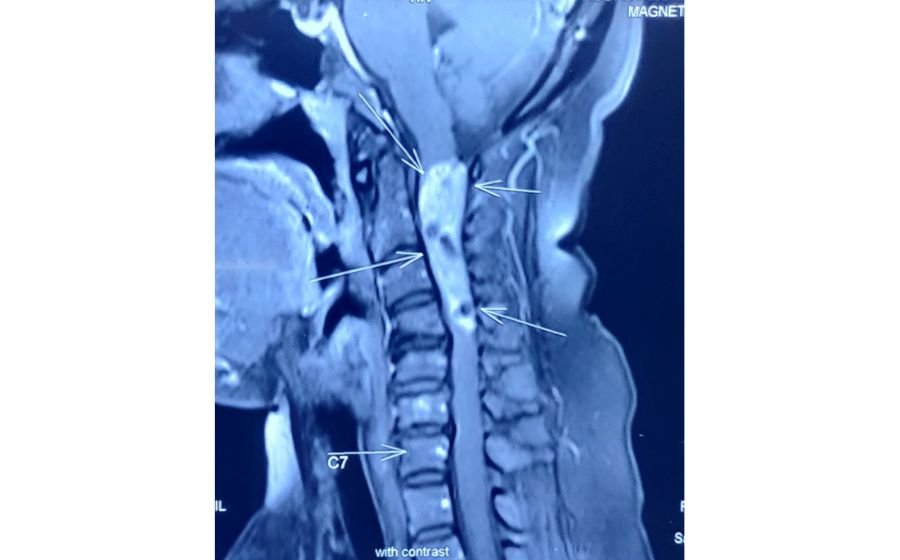

Cervical Myelopathy

Cervical myelopathy occurs when the spinal cord in the neck is compressed due to disc degeneration, ligament thickening, or arthritis. This pressure can cause imbalance, hand clumsiness, difficulty walking, and weakness in the arms or legs. Early diagnosis with MRI is crucial because symptoms can gradually worsen over time. Treatment focuses on decompressing the spinal cord—often through ACDF, cervical disc replacement, or posterior decompression—to prevent progression and improve function. Surgery aims to protect the spinal cord, restore stability, and enhance mobility and quality of life.